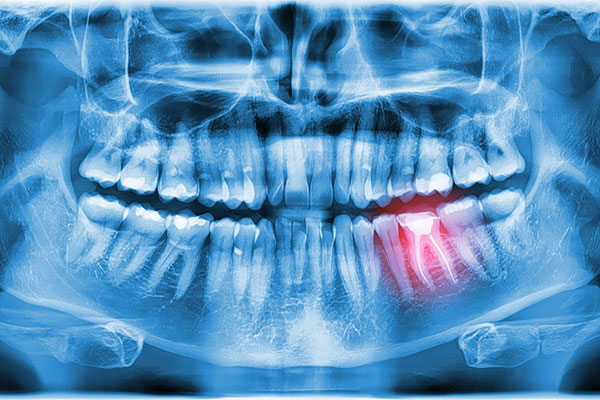

When Would Oral Surgery Be Necessary?

A dentist can take many approaches to treat oral health issues. Lifestyle changes, more frequent cleanings, dental work, and medication may be used. Oral surgery may also need to be incorporated into a patient's treatment plan. Even though healthy alternatives exist that can help reduce pain and improve tooth and gum health, there are circumstances…